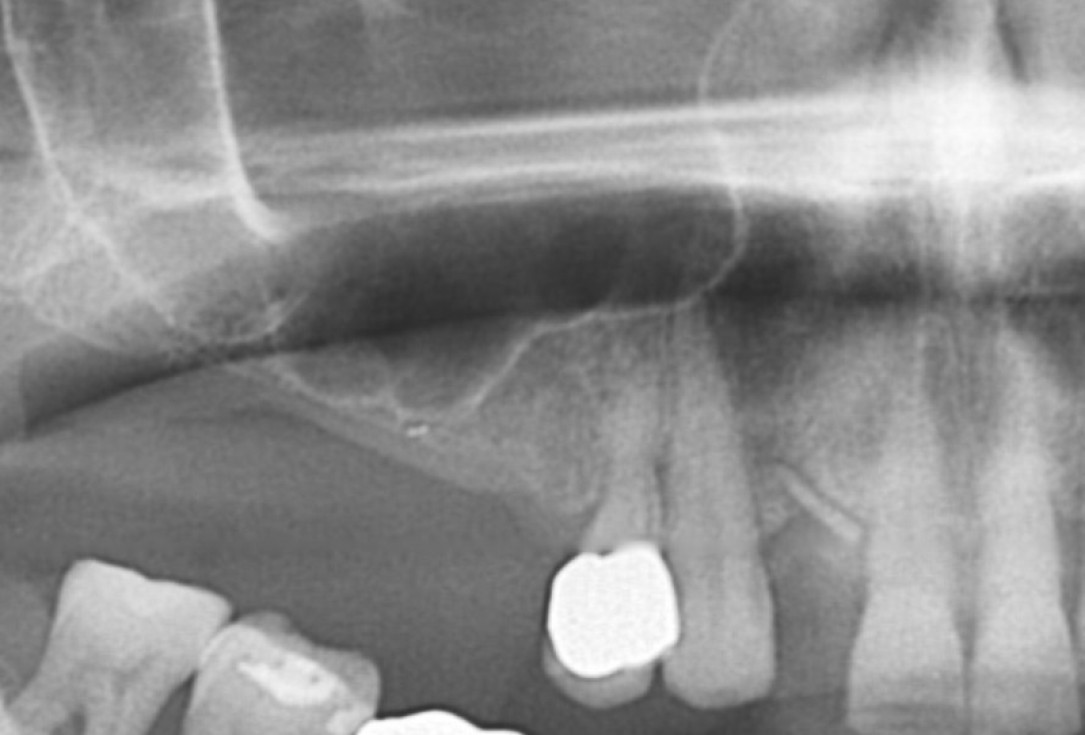

Surgical presentation of the alveolar ridge with reduced amount of horizontal bone available